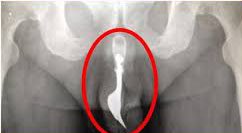

أخر حادثه مسجلة كانت في 1997 لرجل تبول في المياه وتطلب الامر عملية جراحية خطرة لإزالة السمكة من داخل مجرى البول

تقرير عنها

وهذا هو النوع الوحيد الذي من الممكن أن يستهدف مجرى البول بسبب حجمه الصغير ، أما باقي الانواع كبيرة الحجم نسبيا ومفترسة للأسماك

لاحظوا أعدادها